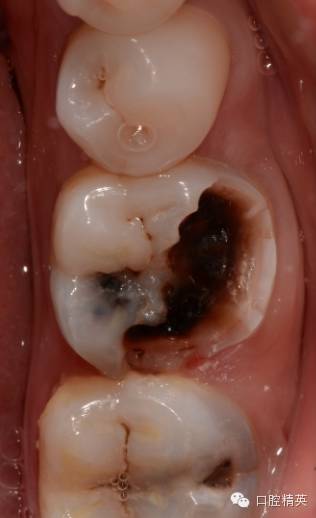

查:36颊he面及远中大面积龋坏,色黑质硬,探敏感,未探及穿髓孔,冷测持续性疼痛,扣无不适,不松,龈正常,对侧同名牙电活力测试值38,36电测牙髓活力值11。37颊侧龋,探敏感,未探及穿髓口,冷测一过性疼痛,扣无不适,不松,龈正常。

诊断:36慢性牙髓炎急性发作,37深龋

处:必兰阻滞麻醉下,36一次性根充,37树脂嵌体修复

![36的一次性根充]()

36,37均有龋坏,且冷测敏感,很多时候我会使用牙髓电活力测试仪来判断牙髓状态,尽可能减少出现误诊,因为这种不可逆的操作,一旦出现误诊,对患者,对医生都是极大的痛苦。所以尽可能多种方法反复测试,如果实在找不到原因,时间也是一种方法。

颊侧龋坏较大,已经接近齐龈,于是树脂临时假壁修补,帮助橡皮障固定,也增加冲洗液容纳量